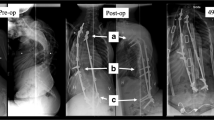

Implantation of device: deformed sheep spine

Implantation of device: deformed sheep spine

All the animals had a similar natural pre-operative spinal curvature (right scoliosis 2º ± 3º, lordosis 3º ± 8º with no difference between groups). In the operatively treated group (group 1) the range of scoliosis treated was 20º–60º and range of lordosis 13º–75º. The device was fitted across this range of deformities satisfactorily. The device was inserted from T5–L1 (n = 5), T4–L1 (n = 1), T4–T12 (n = 1) and T3–T11 (n = 1). A rescue screw was required in L1 in one animal as the 5 mm screw lost fixation and significant bleeding was encountered from the vertebral body. A screw was placed in T4 in a further animal as technical errors with placement in T5 resulted in loss of fixation. All eight animals recovered satisfactorily from the surgery. The animals grew steadily during the period of study and neither tethering to achieve the scoliosis nor subsequent surgery to implant the device adversely impaired development (Fig. 6). Instrumentation of the deformity with the device resulted in immediate correction of the scoliosis from 35° ± 16° to 25° ± 14°, p < 0.01 and correction of the lordosis from 44° ± 20° to 35° ± 18°, p < 0.001 (paired one tailed t test). This is seen in Fig. 7a as an acute decrease in extent of deformity approximately 120 days from birth. At 5 months post-device insertion (day 289 ± 7 post birth) the mean scoliosis was 20º ± 12° and the mean lordosis was 34° ± 22° (Table 2 and Fig. 7a, b). There was no statistically significant difference between these measurements and the immediate post-implantation measurement (p = 0.09, p = 0.43 respectively, paired one tailed t test) although scoliosis had diminished at day 214 ± 5 after instrumentation to 14° ± 14º (p = 0.04). By comparison, the maximal variation in measurements at any time point in the control (no tether, no implant) animals (group 4) for scoliosis was 3° and for lordosis 5°.